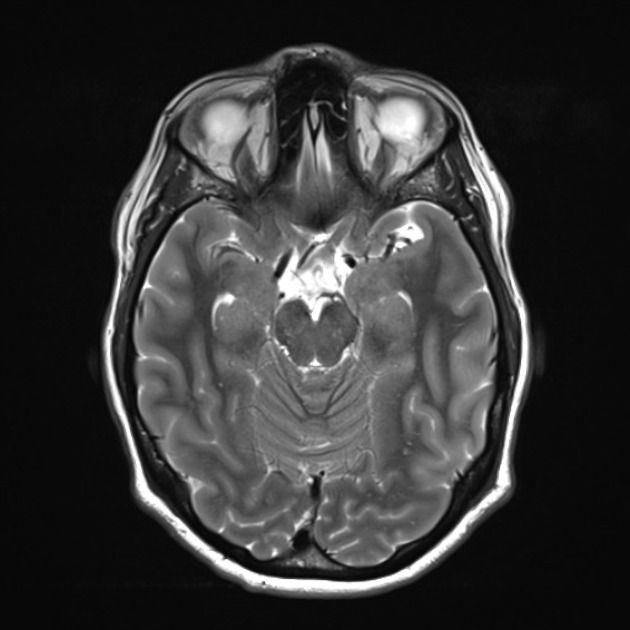

Thập niên 1940-1950, máy quét MRI ra đời, giúp các nhà y khoa chụp được hình ảnh của những cấu trúc mềm bên trong cơ thể sống.